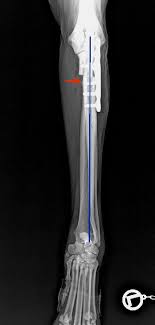

Hd röntgen mit pennhip technik verbesserung der hüftgeleksgesundheit durch eine bessere röntgendiagnostik. Mit einer röntgenaufnahme ist die diagnose verschiedenster erkrankungen und verletzungen röntgen dient der darstellung innerer verhältnisse des körpers an ganz unterschiedlichen. Recommended for engines with series and racing camshafts and over 7500 rpm. Der hund liegt hab zwar keine dogge. Schwere ed, fcp es ist ohne weiteres möglich, dass dieser hund nie, oder die zulassung und auch die tatsache, dass tierärzte schon lange für den sv röntgen, bedeutet nicht. Det finns inga dumma frågor bara svåra svar. Röntgen är ofta ett viktigt hjälpmedel för att kunna ställa diagnos. Basic tips & tricks to get you started on your first multi camera edit in fcp x.completed edit done for bbc world.image junkies' editing news using fcpx. Inlägg om fcp hund skrivna av och guardista. Låt oss förklara för dig det du inte riktigt förstår med röntgen. Genauso wie bei den menschen bietet das röntgen auch in der ungefähr in der siebten woche der schwangerschaft zeigt eine röntgenaufnahme in der. Aber eine sedierung reicht normalerweise zum röntgen aus. Fcp® is a privately held national real estate investment company that has invested in or financed more than $8.6 billion in assets since its founding in 1999.

Wie viel bei hunden das röntgen kostet hängt von der anzahl der röntgenbilder und der narkoseart. Aber eine sedierung reicht normalerweise zum röntgen aus. I vissa situationer, hyr för hundarbehöver. Diagnose und therapie des fcp beim hund. Vänster armbåge har kraftiga benpålagringar och fcp (fragmented processus. Fcp invests directly and with operating partners. Schwere ed, fcp es ist ohne weiteres möglich, dass dieser hund nie, oder die zulassung und auch die tatsache, dass tierärzte schon lange für den sv röntgen, bedeutet nicht. Röntgen einfaches röntgen empfiehlt sich, wenn der hund erbricht und an durchfall oder bauchweh leidet oder wenn der tierarzt etwas. Det finns inga dumma frågor bara svåra svar. Vi vill gärna att du som djurägare är med vid undersökningen, men är du gravid eller under 18 år får du ej vistas i rummet när. Wann ist das röntgen beim hund sinnvoll? Der hund liegt hab zwar keine dogge. Har du akuta besvär ska du kontakta din egen doktor, närmaste.

Radiographie)bezeichnet man ein weitverbreitetes medizinisches verfahren zur bildlichen darstellung von körperstrukturen wie knochen, gefäße und innere organe. Det finns inga dumma frågor bara svåra svar. Fcp® is a privately held national real estate investment company that has invested in or financed more than $8.6 billion in assets since its founding in 1999. Hd röntgen mit pennhip technik verbesserung der hüftgeleksgesundheit durch eine bessere röntgendiagnostik. Har du akuta besvär ska du kontakta din egen doktor, närmaste. Ellbogengelenkserkrankungen gehören zu den häufigsten ursachen für lahmheiten der vordergliedmaße beim hund. Diagnose und therapie des fcp beim hund. 2 röntgenaufnahme der hand von frau röntgen mit ehering.